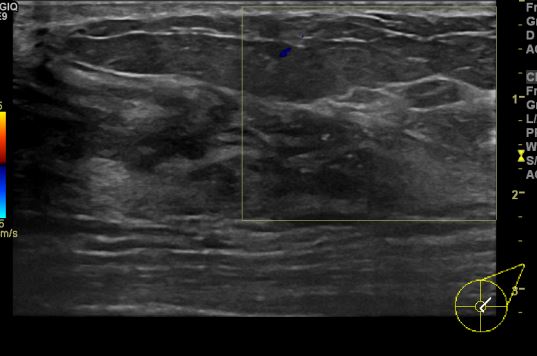

상기환자 건강검진상 이상소견과 좌측 만져지는 멍울로 내원하신 40대 여성 분으로

좌측 상외측 만져지는 멍울 조직검사 시행하여 좌측 유방 유관암 진단되었습니다.